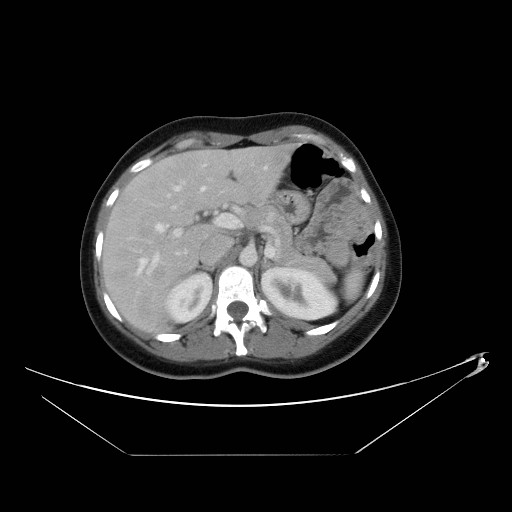

3. 영상 진단 (Localization)

• CT / MRI: 약 70~80% 발견 (hyperdense pancreatic mass)

• Endoscopic US (EUS): 민감도 ~90%, 췌장 내 위치 확인에 유용